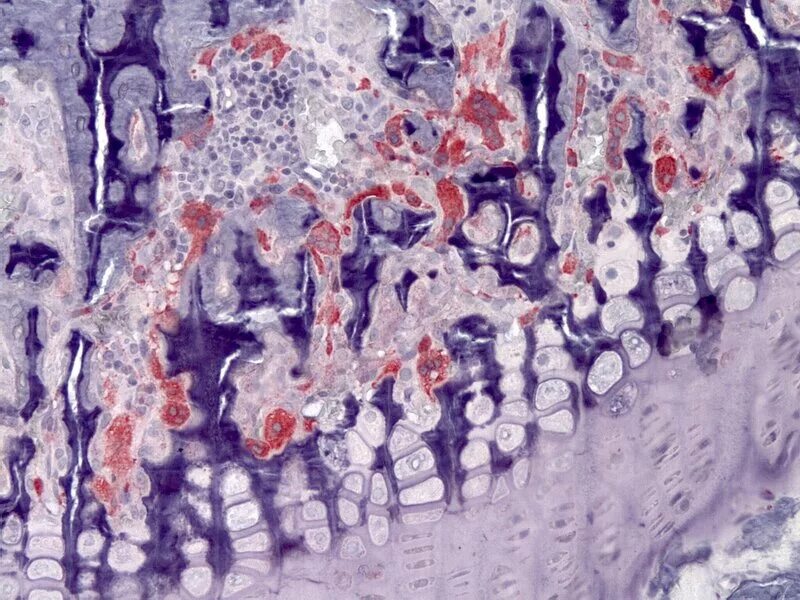

Гистологические исследования тканей